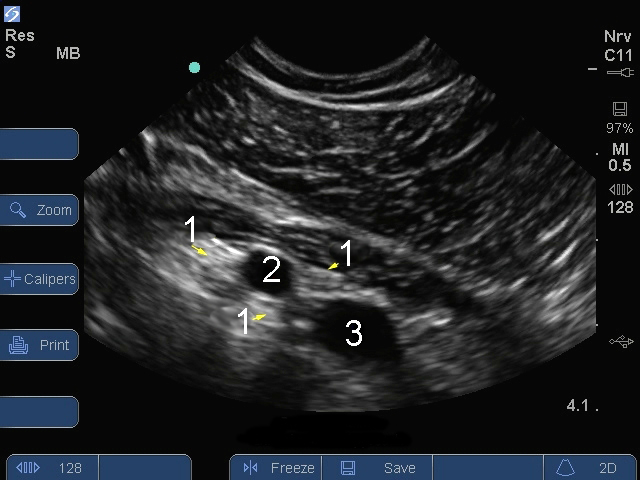

Sシリーズ:腕神経叢鎖骨画像

神経

動脈

静脈